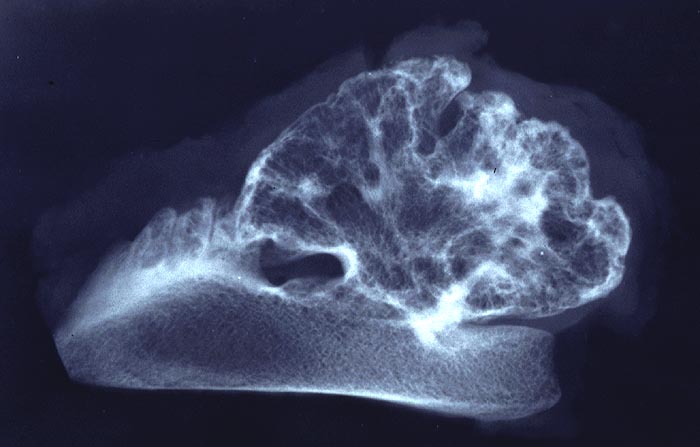

PathoPic – image database / PathoPic ID 5033 - Osteochondrom

Osteochondrom

benigner Tumor

Knochen, Becken

Präparatradiographie: gestielter exophytischer Tumor mit knolliger Oberflächenkontur. Der knöcherne Stiel stellt sich dar wie normale Spongiosa. Die knorplige Oberfläche ist im Nativ-Röntgenbild nicht abzugrenzen.

Makroskopischer Befund: Auf der Sägeschnittfläche des grösseren Präparates erkennt man

scharf abgesetzt vom blutbildenden braunrötlich verfärbten Mark

des Beckenkammes einen blumenkohlartig gestalteten Tumor, der in

seiner Peripherie eine teils unterbrochene max. 0.3cm dicke

Knorpelkappe aufweist. Diese zeigt grauweisse stippchenförmige

Verkalkungen.

Exostose Beckenkamm li. DD: Kartilaginäre Exostose.